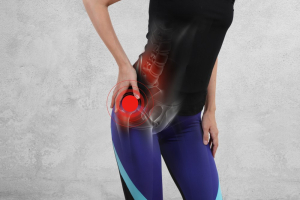

La trocanterite, nota anche come borsite trocanterica, è un’infiammazione della borsa situata vicino al grande trocantere del femore. La trocanterite è una delle principali cause di dolore laterale all’anca. La trocanterite colpisce frequentemente le persone attive, soprattutto le donne tra i 40 e i 60 anni, e può compromettere in modo significativo la qualità della vita.

La trocanterite è una patologia abbastanza comune. Infatti, questa colpisce soprattutto individui di mezza età o anziani, ma anche persone più giovani che praticano particolari sport. Questa malatti, se non opportunamente curato, questo stato infiammatorio può diventare molto doloroso e invalidante.

La causa scatenante dell’infiammazione trocantere è una frizione anomala fra le inserzioni dei muscoli sul grande trocantere e la borsa sinoviale. Quindi, comunemente le cause sono:

I sintomi della trocanterite

Comunemente, la trocanterite si manifesta con dolore all’anca, dolore al gluteo, all’inguine, al fianco, a volte lungo la coscia, al femore, sul lato esterno. In particolare, questa sensazione dolorosa (accompagnata anche da un senso di rigidità articolare) generalmente peggiora quando ci si sdraia sul fianco o si pratica attività fisica anche molto leggera, come una semplice camminata. Tale dolore può essere intenso anche quando ci si alza in piedi dopo essere stati a lungo seduti.

Se non si interviene con trattamenti adeguati, il dolore all’anca può diventare così intenso da rendere estremamente difficoltose le normali attività quotidiane: camminare, fare le scale o stare seduti a lungo in ufficio. Quindi non bisogna sottavlutare questi segnali.